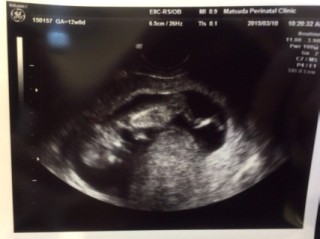

エコー写真

顔

• おなまえさあちゃん

• ねんれい21歳

• 妊娠週12w0d

始めての腹部エコー( ´ ▽ ` ) 始めて心臓の音も聞こえて感動しました♪ 指をしゃぶったり かわいい(。-_-。) 元気に育ってね。